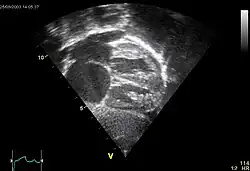

Erworbene Aortenstenose

Ät.: Degenerativ, rheumatisch

Makro: Die Taschenklappen sind plump verdickt, verkalkt und fusioniert. Die Querschnittsfläche ist verkleinert (< 2,5 cm²).

Klinik: Leistungsminderung, Belastungsdyspnoe, Synkopen, Schwindel.

Kompl.: Bakterielle Endokarditis, KHK (konzentrische Druckhypertrophie des Myokards mit relativer Koronarinsuffizienz), Linksherzinsuffizienz (-> Lungenstauung, Lungenödem),.

![]() |